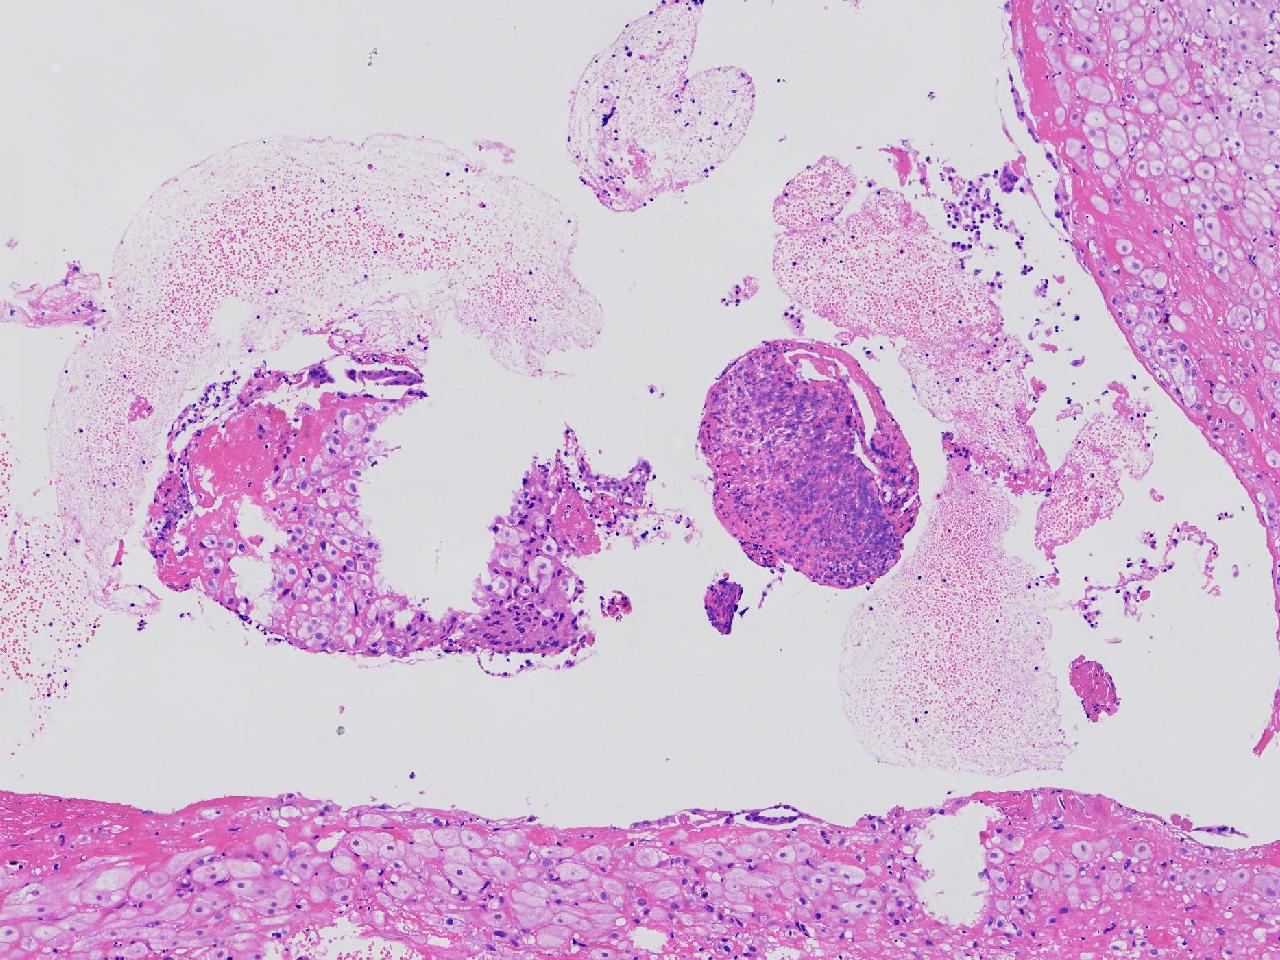

女,29岁,药物流产20余天,阴道少量出血20余天。行诊刮术。

宫腔内容物

灰粉色不整形软组织多块,4X3X3厘米,部分为血凝块。

送检组织为胎盘绒毛及蜕膜组织及滋养层细胞考虑为不全流产